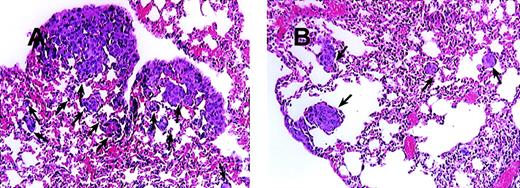

Blocking MCP-1 enhances the survival of SCID mice bearing MDA-231 human breast carcinoma cells

On the basis of the fact that MCP-1 is abundantly produced by tumor cells, we wanted to evaluate the contribution of MCP-1 toward tumor growth. We, therefore, selected a human breast carcinoma cell line MDA-231 to study the effect of a MCP-1 antibody on tumor growth. The MDA-231 cell line produced approximately 6500 pg of MCP-1/mL, when cells were grown at a concentration of 0.5 × 106 cells/mL of RPMI for 24 hours as determined by enzyme-linked immunosorbent assay (data not shown). MDA-231 cells were then injected intravenously into SCID mice, as described in the “Materials and methods” section. As shown in Figure 6, administration of MCP-1 antibody significantly increased the survival of SCID mice bearing MDA-231 carcinoma tumors in contrast to mice treated with control antibody (P < .024). Neither administration of exogenous MCP-1 nor antibodies to MCP-1 had an effect on the growth of MDA-231 cells in vitro (Table 2). Analysis of the metastatic lesions in the lungs revealed that the experimental micrometastases therein were significantly smaller and lower in number when treated with the MCP-1 antibody than in the control antibody group (Figure 7). As shown in Figure 8, grading analysis of the lung metastasis by calculating the total area invaded by the tumor in each mouse indicated that the group of mice treated with control antibody exhibited about 2.5 times more metastases than the group of mice treated with anti-MCP-1. The metastatic index of control-treated mice was 0.146 (SEM ± 0.027), whereas the metastatic index of anti-MCP-1–treated mice was 0.057 (SEM ± 0.011; P < .005). These data demonstrate that the size and number of metastatic lesions formed in the presence of antibody to MCP-1 are reduced, and increases in survival were observed, indicating that MCP-1 has a role in tumor progression.

Blocking of MCP-1 inhibited lung tumor metastases of SCID mice bearing MDA-231 human tumor breast cancer cells.

SCID mice were injected intravenously with 20 μL of antiserum to ASGM1 on day 0, and 3 × 105 MDA231 human breast carcinoma cells were injected intravenously on day 1. Antibodies, including rabbit IgG (panel A) and 279 Ab (Panel B) at 25 μg/mouse (1 mg/kg), were given intraperitoneally to the mice on days 4, 8, 12, 16, 20, 24, and 28. For experimental metastasis experiments, mice from both groups were sacrificed on the 35th day after intravenous injection of the tumor cells. Lungs were extracted and fixed in formalin. Histological sections were stained with hematoxylin and eosin to evaluate tumor metastases. Photographs were taken at 150× magnification. The arrows indicate metastatic lesions. One representative field from 2 experiments is shown.